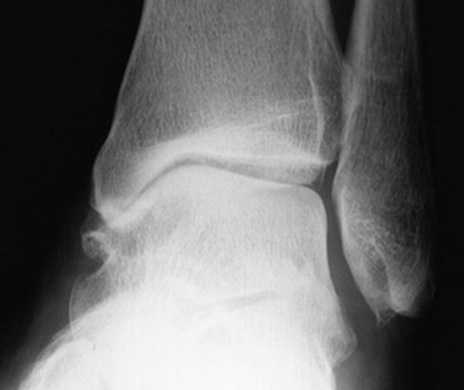

Классификация артроза голеностопного сустава.

Дальнейшее сужение суставной щели в медиальной части сустава до контакта субхондральной кости

Сужение суставной щели в области крыши купола таранной кости до контакта субхондральной кости

Для диагностие выполняются рентгенограммы в прямой, боковой и косых проекциях, с нагрузкой весом тела. На рентгенограммах определяется сужение суставного пространства, субхондральный склероз, формирование кист, деформация, рост остеофитов.